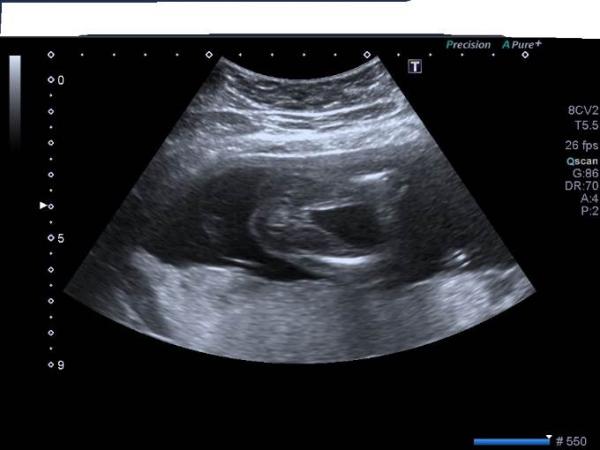

Ich hatte auch genauso ein Bild aber es sieht nach junge aus habe nämlich dieses Bild bekommen und es wurde ein Mädchen das sieht mehr nach junge aus

Bild zu